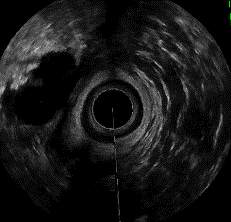

肛門超音波検査

お尻から専用の超音波装置を挿入し、肛門の筋肉や内側の壁の層構造を観察します。

主に肛門括約筋の状態や肛門周囲膿瘍(のうよう)の有無、痔瘻(じろう)の走行像などの評価に用います。